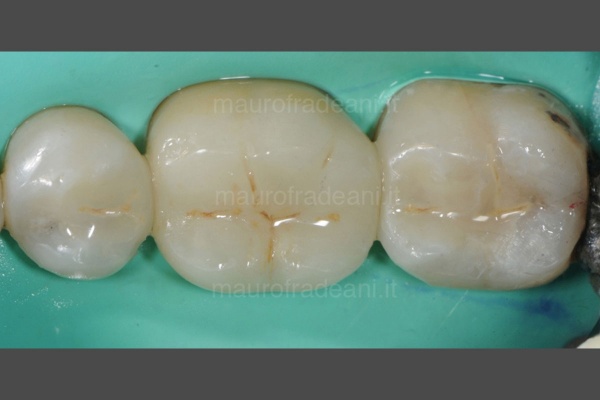

Dental sealants

1/3: The presence of deep grooves on the teeth surface makes its cleaning difficult and enhances bacterial growth, leading to an increasing risk of tooth decay. The sealing of permanent teeth is a preventive treatment which isolates the grooved and creates a barrier against bacteria.

2/3: This quick and painless operation does not require anesthesia. The treated tooth has to be isolated with a rubber dam preventing contamination.

3/3: The dental sealant, applied with a brush, is a special white-transparent resin with continuous release of fluoride ions. This material guarantees enamel protection for several years and can be newly applied in case of damage.